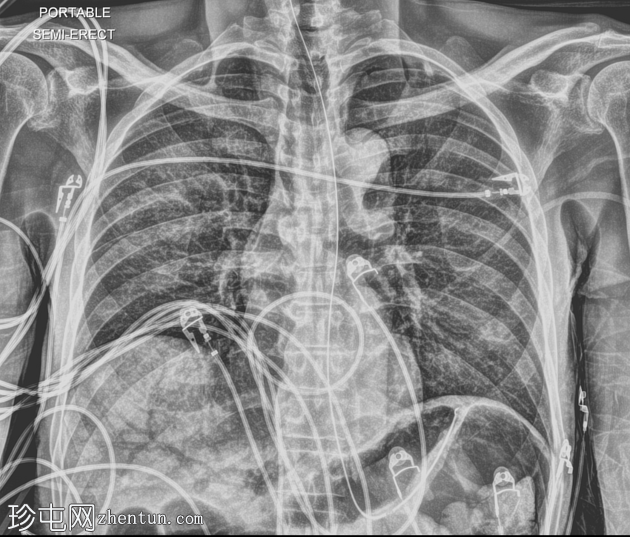

X线片

正位片